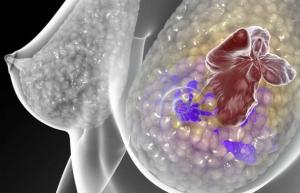

Une patiente sur 5 environ atteintes de cancer du sein, présente un nombre supérieur à la moyenne de récepteurs HER2 à la surface des cellules tumorales. Ces récepteurs sont des molécules qui envoient des signaux de croissance dans la cellule. La surabondance de ces récepteurs HER2 pousse les cellules cancéreuses à se diviser et la tumeur à se développer ainsi plus rapidement.

L’émergence des conjugués anticorps-médicament (CAM): Depuis quelques années, une nouvelle classe de médicaments, les conjugués anticorps-médicament sont testés dans le traitement des cancers. lls sont constitués d’un anticorps et d’un médicament : L’anticorps se lie à une molécule cible présente à la surface de la cellule tumorale – ici HER 2- par son extrémité variable tandis que son extrémité constante est armée d’un médicament. La cellule tumorale absorbe l’anticorps qui délivre le médicament qui détruit la cellule cancéreuse de l’intérieur.

En association avec une immunothérapie : L’idée ici est de combiner un CAM, » trastuzumab emtansine « , un anticorps ciblant le récepteur HER 2 couplé à un cytotoxique, avec une immunothérapie supplémentaire qui active le système immunitaire pour attaquer la tumeur de manière encore plus efficace. Les chercheurs, dirigés par le Pr Alfred Zippelius de l’Hôpital universitaire de Bâle ont testé cette thérapie doublement combinée chez des souris modèles de cancer du sein. L’équipe montre que la thérapie parvient à bloquer les récepteurs sur les cellules immunitaires qui amortissent leur activation et, en administrant un anticorps complémentaire, à restaurer l’activation de différentes cellules immunitaires. Si seule, cette réponse immunitaire n’a pas d’effet immédiat et suffisant sur la tumeur du sein, en combinaison avec le CAM, elle se révèle efficace pour attaquer les cellules cancéreuses au point d’entraîner une guérison complète. Les chercheurs démontrent également que dans ce cadre, les cellules-T régulatrices jouent un rôle de protection de l’hôte.